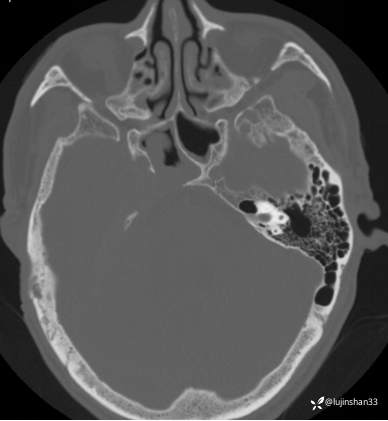

(2023-05-29 16:07,本院)CT颅脑:1、右侧颞骨全切除术后改变,术区见气体密度影,瘘管形成可能;术区多发软组织影,不完全除外炎性改变可能。2、左侧颞骨CT平扫未见明显异常。